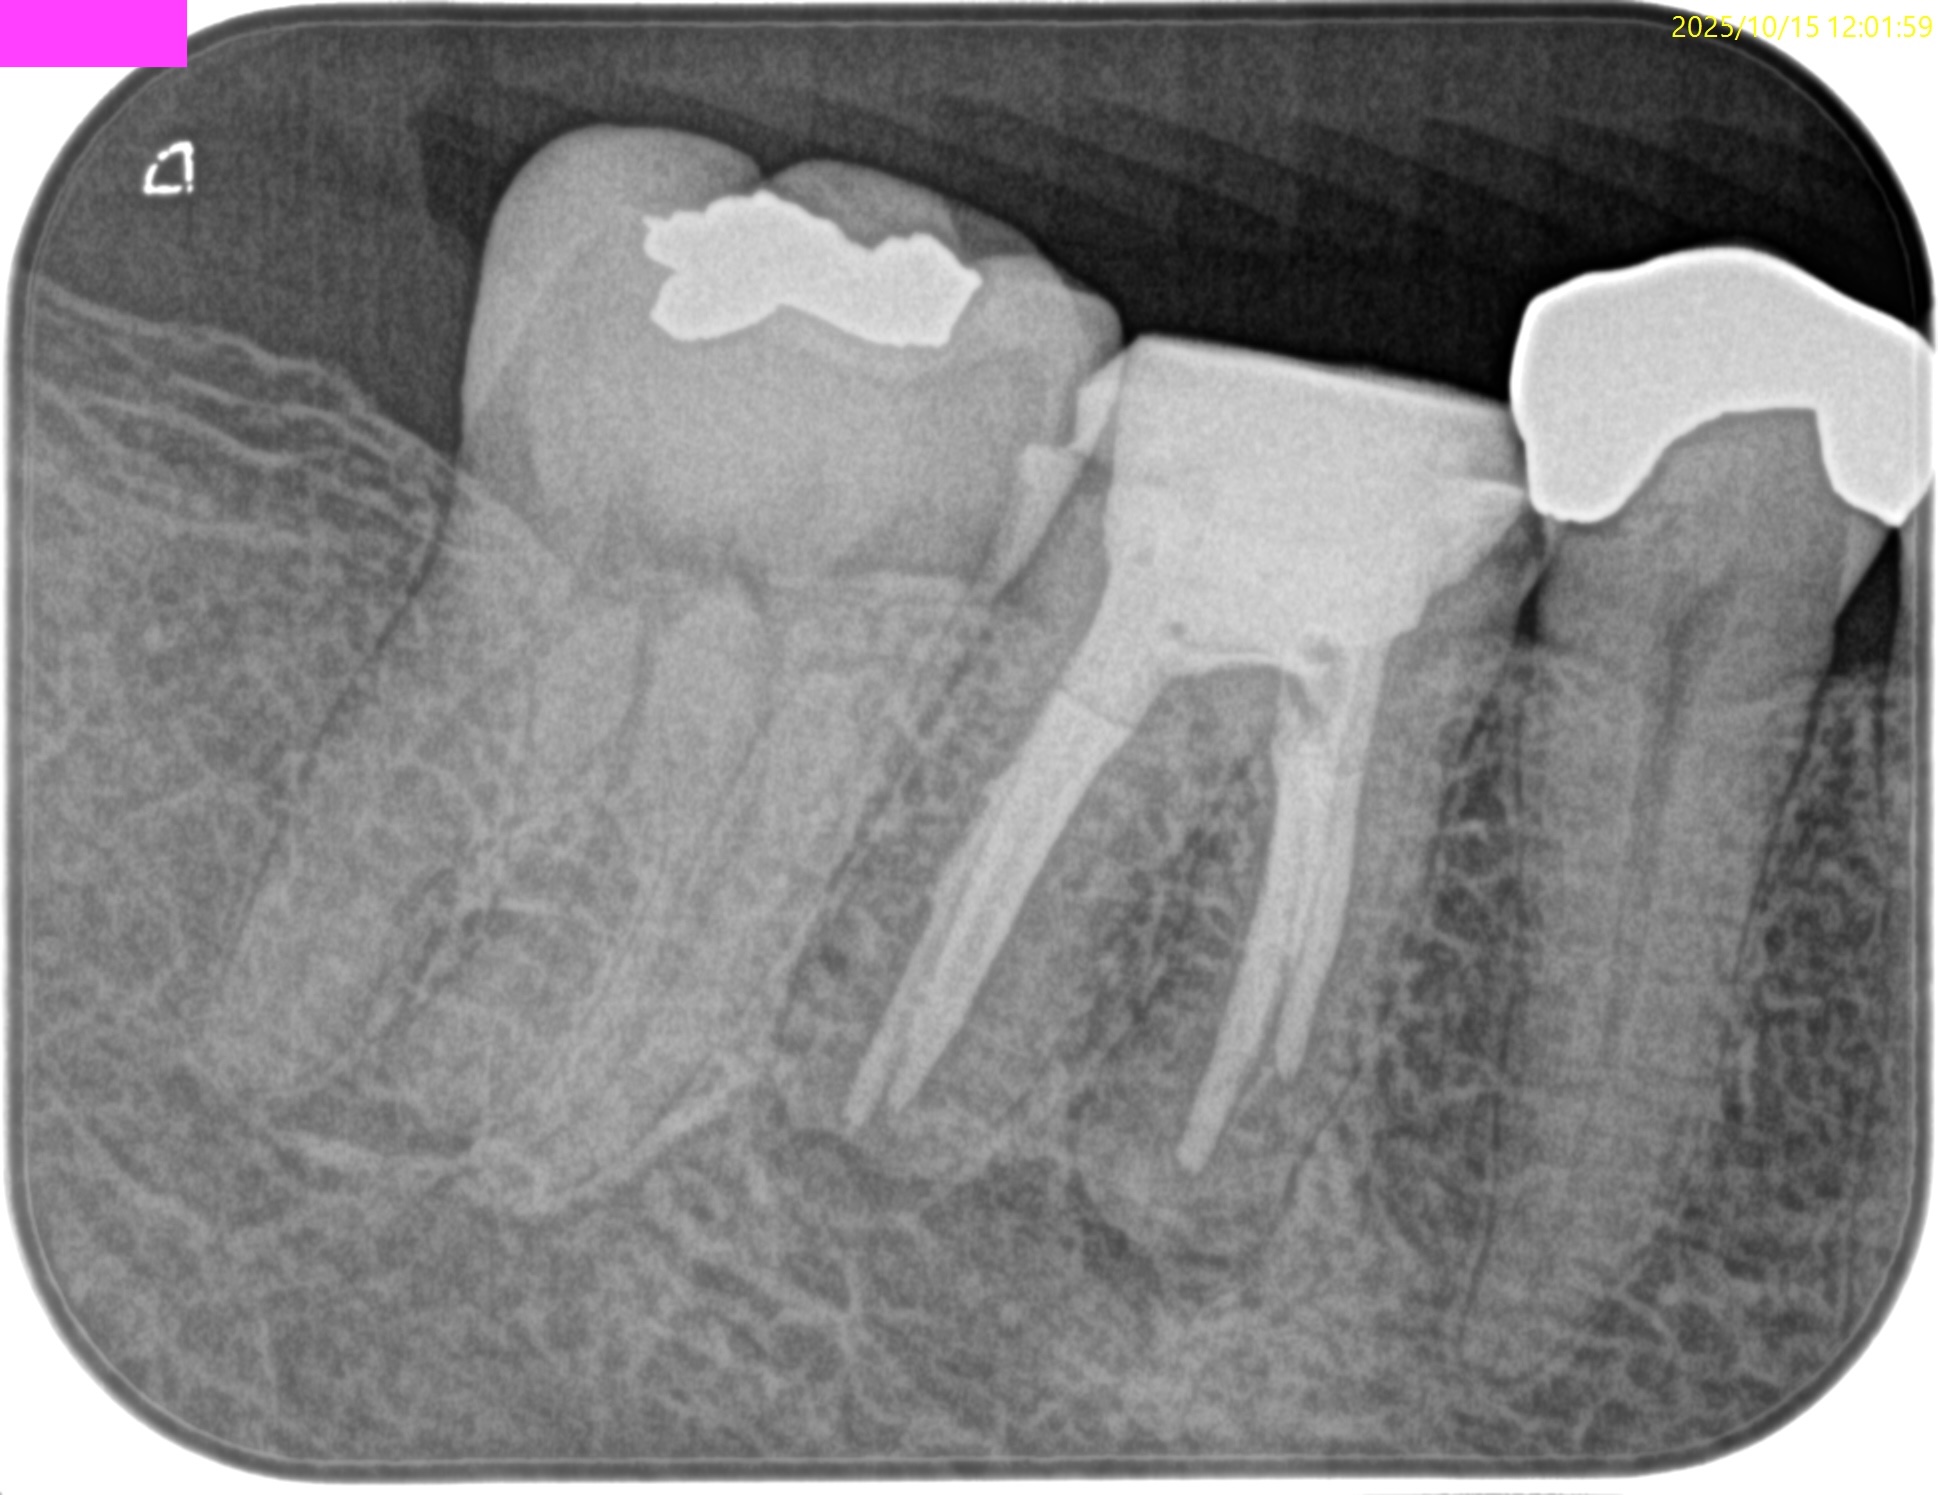

術後にPA, CBCTを撮影した。

MB

ML

D

B

MLは穿通しなかったがこれは細かいGutta Percha Pointが残存したか?破折ファイルの存在か?もしれない。

破折ファイルならば、それは私が折ったのか?前医なのか?はわからないが、

そこにはエンドの予後に与える影響はほぼないことはこのBlogの愛読者?ならご理解いただけるだろう。

患者さんにはこのことを告げた。